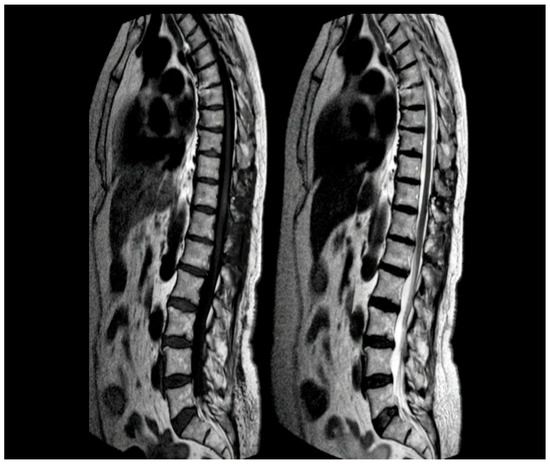

Figure 1.

MRI of the thoracic spine. Left: T1-weighted image showing the expansive lesion at the T11 level (red arrow). Right: T2-weighted image revealing the lesion with surrounding edema (yellow arrow).